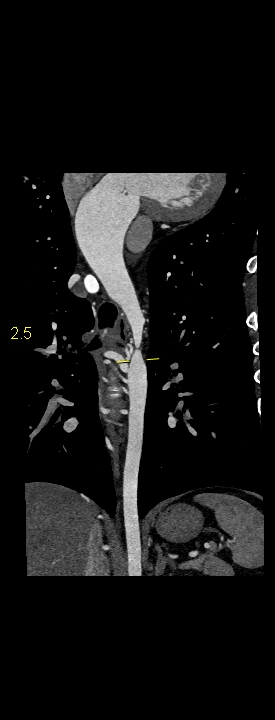

Figurile 1-5: reconstrucții multiplanare din achiziție angioCT aorta toracică

Discuţie caz nr 109: Pacient cu suspiciune de coarctaţie de aortă – are indicație de angioCT aortă toracică; medicul radiolog la acești pacienți este indicat să efectueze investigația cu sincronizare ECG deoarece coarctaţia de aortă poate fi asociată și cu bicuspidie de valvă aortică, mai ales că la acest pacient ecografia cardiacă descria creștere de calibru a aortei ascendențe. Pe reconstrucția cine în planul valvei aortice din achiziția cardioCT cu sincronizare ECG se remarcă o valvă aortică morfologic tricuspidă, funcțional bicuspidă ce asociază ectazie de aortă ascendentă și coarctaţie de aortă descendentă cvasicompletă cu dezvoltare de circulație colaterală intercostală și mamară internă.